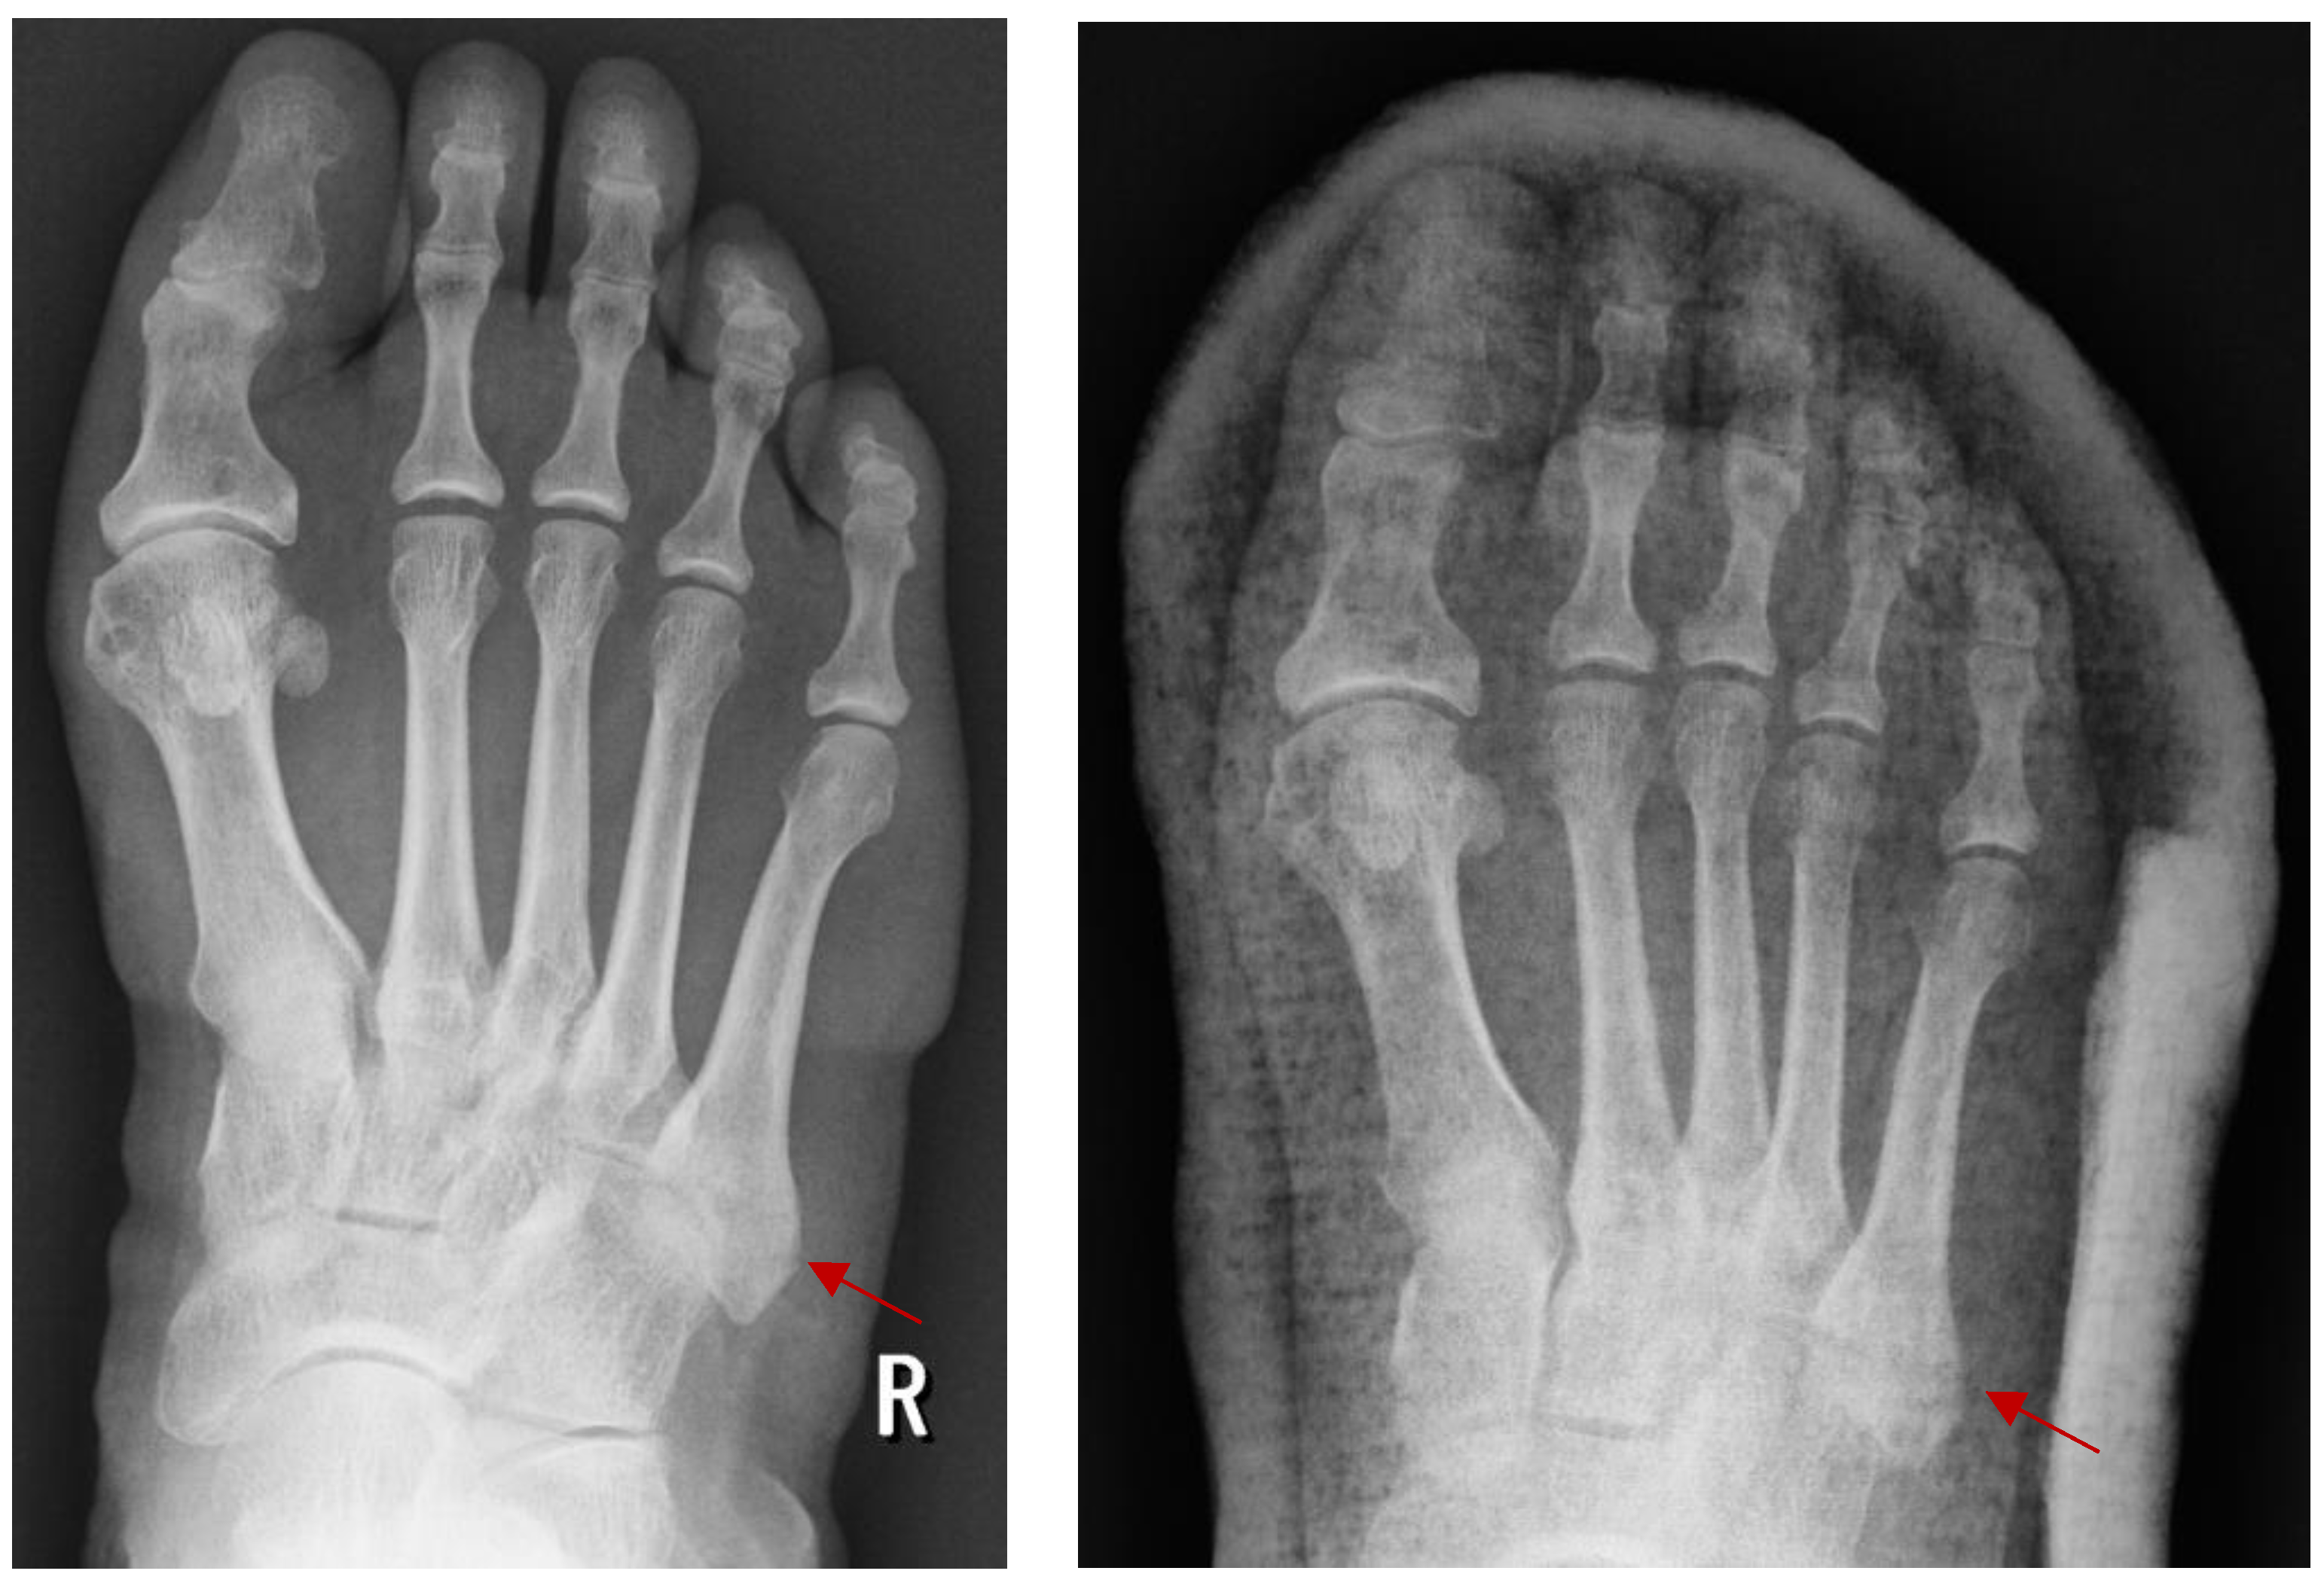

4.1.1. Surgical Management: Open Reduction and Internal Fixation (ORIF)

4.1.2. Minimally Invasive Surgery (MIS)

4.1.3. External Fixation and Arthroscopic Technique